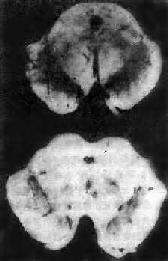

黑质蓝斑脱色是本病肉眼变化的特点(图16-35)。镜下可见该处的黑色素细胞丧失,残留的神经细胞中有Lewy小体形成,该小体位于胞浆内,呈圆形,中心嗜酸性着色,折光性强,边缘着色浅。电镜下,该小体由细丝构成,中心细丝包捆致密,周围则较松散。

图16-35 Parkinson病

中脑黑质脱色(下),正常中脑黑质完好(上)